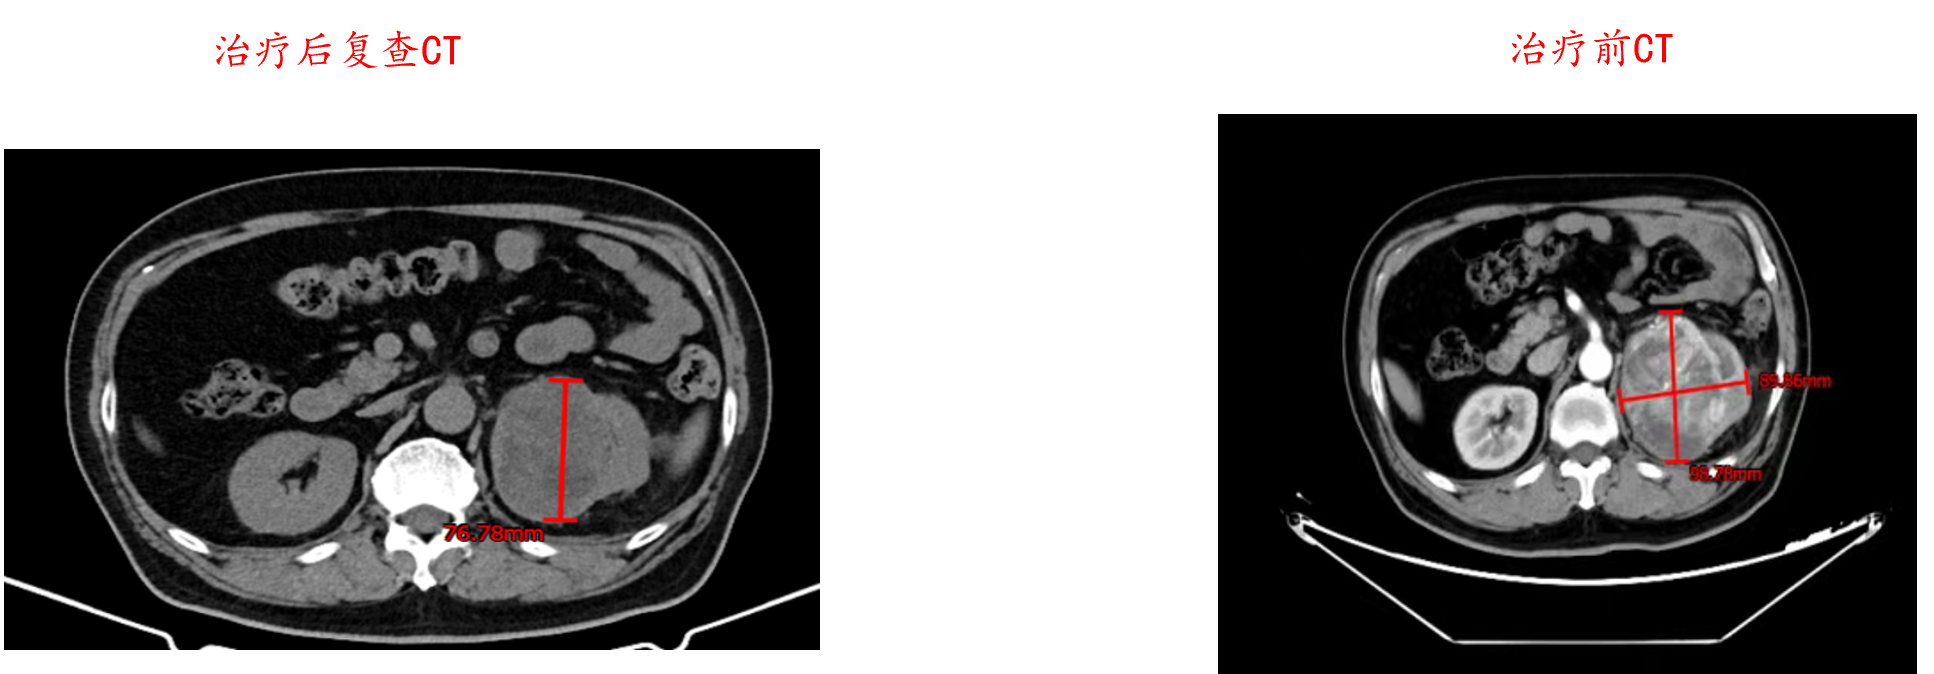

2024年2月25日,给予培唑帕尼(800 mg,po,QD)治疗,持续半年。治疗1周后,患者血尿症状消失。

2024年3月13日,培唑帕尼治疗3周时,影像学检查提示原发灶肿瘤呈缩小趋势。

2024年4月26日,培唑帕尼治疗2个半月时,影像学检查提示原发灶肿瘤显著缩小。

2024年5月27日,培唑帕尼治疗3个半月时,影像学检查提示原发灶肿瘤进一步缩小,切除可能性提高。治疗过程中,患者一般状况良好,无严重不良事件发生,仅出现轻微恶心与呕吐(均为1级)。调整治疗方案,加用骨保护剂药物地舒单抗(120 mg,ih,Q4W)。

疗效评估

2024.11胸CT示与2024.8相比: